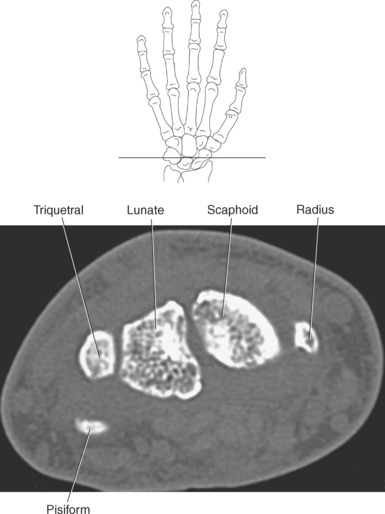

The bony anatomy of the wrist and hand consists of the distal radius and ulna, 8 carpal bones, 5 metacarpals, and 14 phalanges (Figure 9.101). Both the distal radius and ulna have a conical styloid process that acts as an attachment site for ligaments. The radial styloid process is located on the lateral surface of the radius, whereas the ulnar styloid process is located on the posteromedial side of the ulna. The carpal bones are arranged in proximal and distal rows. Located in the proximal row of carpal bones are the scaphoid (navicular), lunate (semilunar), triquetral (triquetrum), and pisiform bones. The pisiform is considered a sesamoid bone that is embedded in the tendon of the flexor carpi ulnaris. The distal row consists of the trapezium (greater multangular), trapezoid (lesser multangular), capitate (os magnum), and hamate (unciform) bones (Figures 9.102 through 9.114). The five metacarpals are small tubular bones with a proximal end (base), distal end (head), and shaft (body). The 14 phalanges that make up the fingers are short tubular bones. Like the metacarpals, each phalanx consists of a proximal (base), middle (body or diaphysis), and distal (head) portion. Each digit consists of 3 phalanges (proximal, middle, and distal), except for the thumb (first digit), which has only 2 phalanges (proximal and distal). The articulation of the phalanges of the second through fifth digits creates three interphalangeal joints: the metacarpophalangeal (MCP) joints classified as condyloid joints, proximal interphalangeal (PIP), and distal interphalangeal (DIP). The proximal and distal interphalangeal joints are classified as hinge joints (Figure 9.101). The first digit, which consists of 2 phalanges, has just two joints: the MCP joint, classified as a saddle joint, and an interphalangeal joint, classified as a hinge joint (Figure 9.101).

The joints of the wrist and hand are quite complex and consist of the following: distal radioulnar articulation, radiocarpal articulation (proximal joint of hand), midcarpal articulation (distal joint of hand), intercarpal articulations (articulations between proximal and distal carpals), carpometacarpal articulations (between carpals and metacarpals), the intermetacarpal articulations (between bases of metacarpals two through five) and the interphalangeal joints (between phalanges of each digit) (Figures 9.111 and 9.115). The distal radioulnar articulation, also called the distal radioulnar joint (DRUJ), is created when the ulnar notch of the radius moves around the articular circumference of the ulna, providing the movements of supination and pronation. The main stabilizing element of the DRUJ is an articular disk called the triangular fibrocartilage complex (TFCC). The TFCC is a fan-shaped band of fibrous tissue that originates on the medial surface of the distal radius and traverses horizontally to insert on the ulnar styloid process (Figures 9.115 and 9.116). It rotates against the distal surface of the ulnar head during pronation and supination and separates the ulna from the carpal bones. The proximal surface of the radiocarpal articulation is formed by the articular carpal surface of the radius and the TFCC, whereas the distal surface is formed by the articular surfaces of the scaphoid, lunate, and triquetrum and the interosseous ligaments connecting them (Figures 9.111 through 9.115). The midcarpal joint is formed by the articulations between the proximal and distal carpal rows (Figures 9.110 and 9.115). The articulation between the carpals within each row creates the intercarpal joints (Figures 9.111 and 9.115). The carpometacarpal joints are formed by the articulations between the carpus and the five metacarpals (Figure 9.111 and 9.115). The carpometacarpal joint of the thumb is an independent joint formed by the articular surfaces of the trapezium and first metacarpal, creating a pure saddle joint. The carpometacarpal articulations of the two to five digits are amphiarthrotic joints with little mobility (Figures 9.105 and 9.115). The intermetacarpal articulation exists between the base of the metacarpals and is joined by the palmar and dorsal metacarpal ligaments (Figure 9.115).